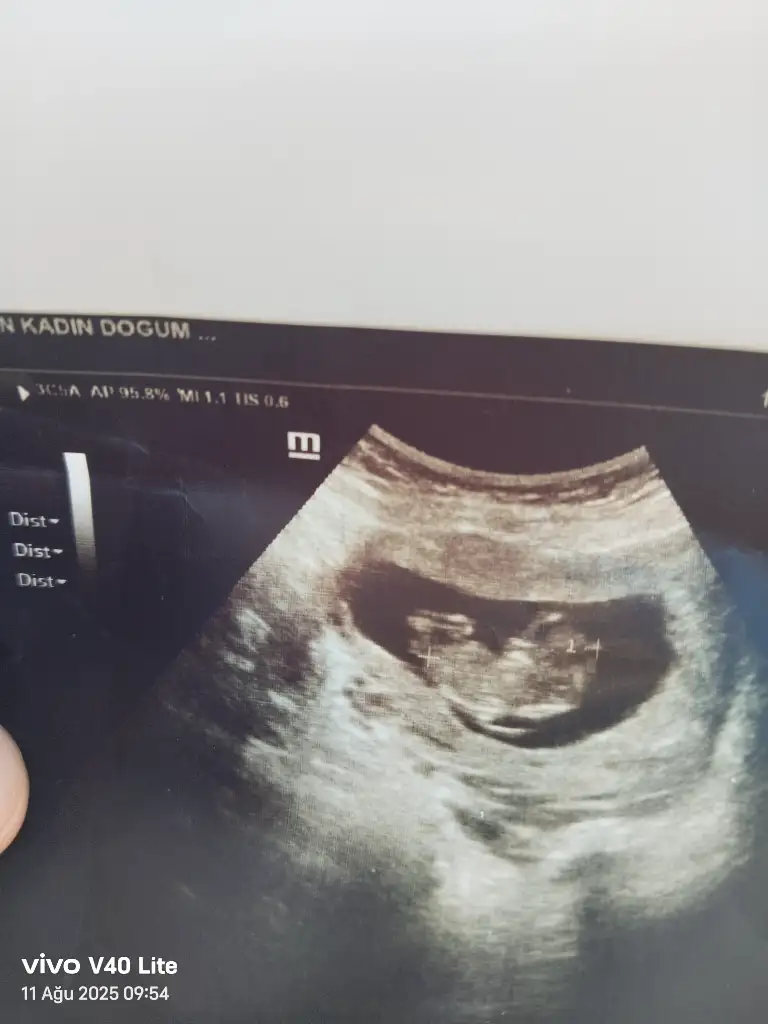

Keseye göre kız ama kese şekliyle bir ilgisi yok aslında benimde sizin gibiydi kesem bebeğim erkek sağlıkla gelsin bebeğiniz

Eklentiler

• 1000022811.webp

22,9 KB · Görüntüleme: 20

• 1000022812.webp

22,9 KB · Görüntüleme: 22

• 1000022810.webp

22,8 KB · Görüntüleme: 20

• 1000022813.webp

24,2 KB · Görüntüleme: 23